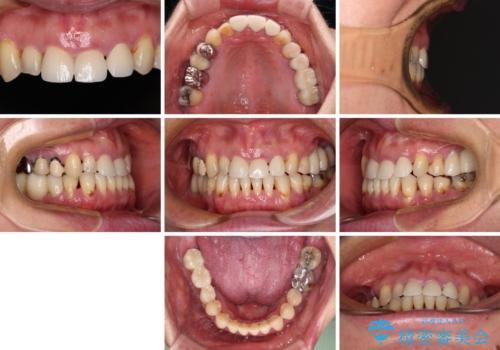

反対咬合や欠損を治療したい インビザライン矯正とオールセラミックブリッジ

- 虫歯治療がうまく進まないとのことで来院された患者様です。

虫歯治療や欠損補綴治療も必要でしたが、前歯が反対咬合であったので、セラミッククラウンやブリッジによる治療と並行して矯正治療を提案しました。

仕事柄海外出張が多いとのことで、虫歯治療後にインビザラインにて矯正治療を行うこととしました。

海外出張にとどまらず海外赴任もあり、途中2度の妊娠もあったため、治療には非常に長い期間を要することとなりました。